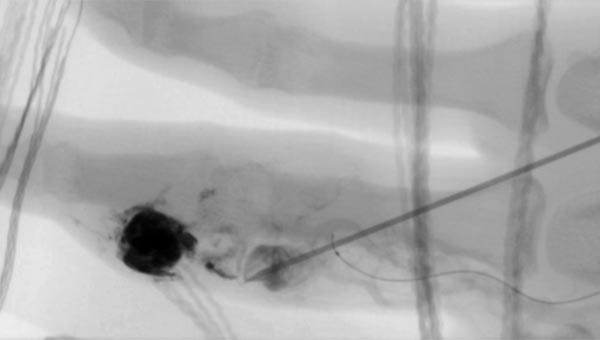

Fluoroskopische Darstellung der Punktionsnadel bei Beginn der direkten perkutanen Embolisationstherapie am Finger mit einem Flüssigembolisat (EVOH). Zusätzlich sichtbar der nicht ganz bis zum Nidus vorgeschobene Mikrokatheter.

Fluoroskopische Abschlußkontrolle nach erfolgreicher Nidusembolisation der AVM. Der transarteriell von brachial eingebrachte Mikrokatheter wurde während der perkutanen Embolisation als Landmarke für die zuführende Arteria digitalis propria belassen. Zusätzlich sichtbar röntgendichte Markierungen durch auf der Haut aufliegende Kompressen.